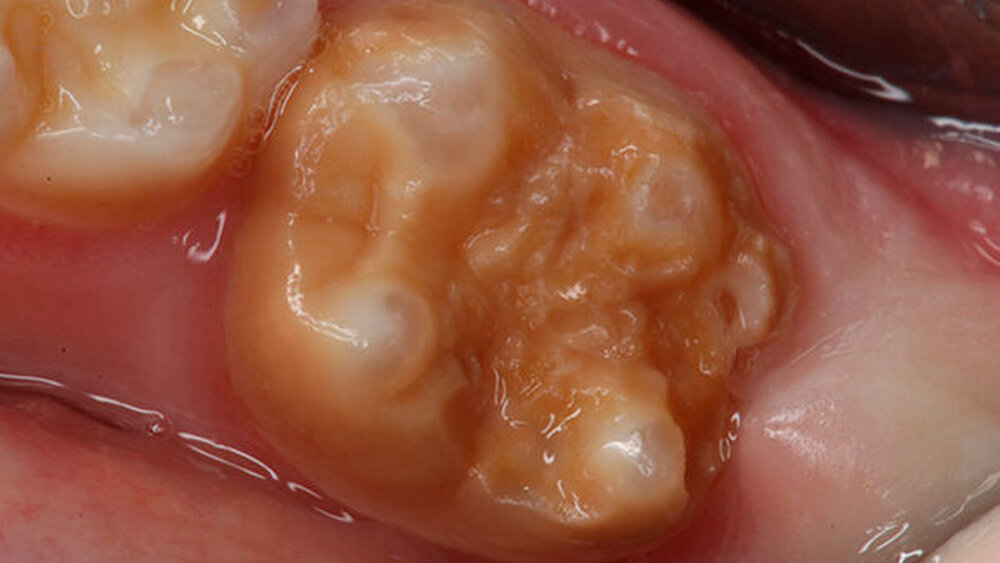

In Deutschland sind laut der fünften Deutschen Mundgesundheitsstudie (DMS V) etwa 10 bis 15 Prozent aller Grundschulkinder und knapp 30 Prozent der 12-jährigen Kinder von MIH betroffen.(1) Bei der Behandlung ist viel Fingerspitzengefühl gefragt: Die jungen Patienten können unter hypersensiblen Zähnen leiden und dies beeinträchtig häufig auch die tägliche Mundhygiene. Hinzu kommt die schmerzempfindliche Reaktion auf Hitze, Kälte und Zähneputzen. Letzteres konterkariert die Therapie, denn die betroffenen Zähne haben einen erhöhten Behandlungsbedarf. Sie können durch den Schmelzdefekt besonders kariesanfällig sein. Zudem reagieren die betroffenen Kinder aufgrund der Schmerzen zum Teil eingeschränkt auf die Lokalanästhesie, was die Therapie erschwert.

Nach den konkreten Ursachen für die auch als „Kreidezähne“ bezeichnete Strukturanomalie der bleibenden Zähne wird noch geforscht. Als sicher gilt, dass die ersten Lebensjahre einen entscheidenden Einfluss auf die Entwicklung der MIH haben, da in dieser Phase die Mineralisation der Kronen der ersten bleibenden Molaren und Inzisivi stattfindet.(2)

Bei einer schweren MIH können kleinere Fissuren einfach und schnell mit dem flüssigen Glasionomer-Oberflächenschutzmaterial GC Fuji Triage zum Schutz vor Karies abgedeckt werden. Das Verfahren ist für die Patienten schmerzlos und minimalinvasiv. Bereits eingetretene, größere Defekte können mit den Füllungsmaterialien EQUIA Fil (Glasionomer) und EQUIA Forte HT (hochviskoses Glas-Hybrid) versorgt werden. In einigen Fällen ist bei einer schweren MIH eine definitive Füllung aufgrund des Defektes nicht möglich. Hierfür eignet sich ergänzend zu Glasionomeren die Behandlung der Überkappung mit Edelstahlkronen, die zudem mit Glasionomer befestigt werden. Sie dient als Übergangslösung, bis eine definitive Versorgung durch eine indirekte Restauration möglich ist.